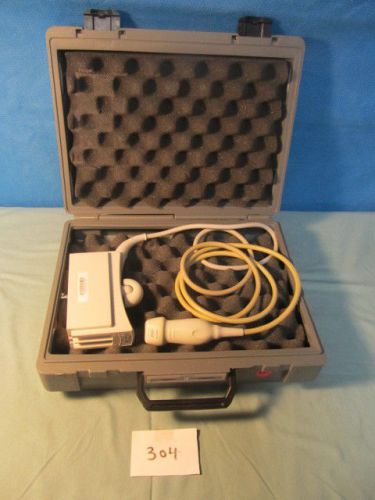

Acuson 3V2C Adult Cardiac Array Probe Transducer Ultrasound for Sequoia

Acuson 15L8w Linear Array Probe for Acuson Sequoia System

Acuson 10V4 Pinless, 7V3C Cardiac &4C1 Curved Probe for Sequoia Systems (QTY-3)

Philips 21253A C3540 Transducer